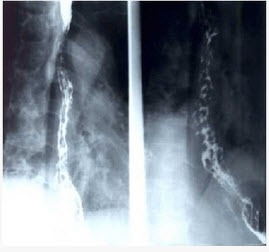

男性,胸骨后隐痛一年,请选择正确答案()